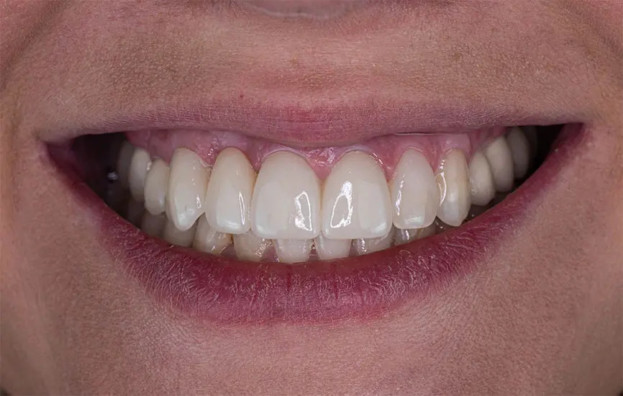

– велика естетичність, що особливо важливе для передніх зубів;

– збереження природного ясенного контуру;

– найкращий косметичний результат, зниження ризику інфікування у процесі процедури;